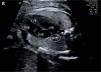

A 21-year-old, primigravida, without relevant personal or family history, was referred at 28 weeks of gestation for echocardiographic examination due to fetal arrhythmia, not confirmed. However, in the same exam an isolated right aortic arch was detected (figures A and B). The authors present the images.

Figure A.

Right aortic arch passing posterior to the trachea. AO: aorta; PA: pulmonary artery; RV: right ventricle; SVC: superior vena cava; TR: trachea.

Figure B.

4-chamber view of the fetal heart. AO: aorta; LA: left atrium; LV: left ventricle; RA: right atrium; RV: right ventricle.